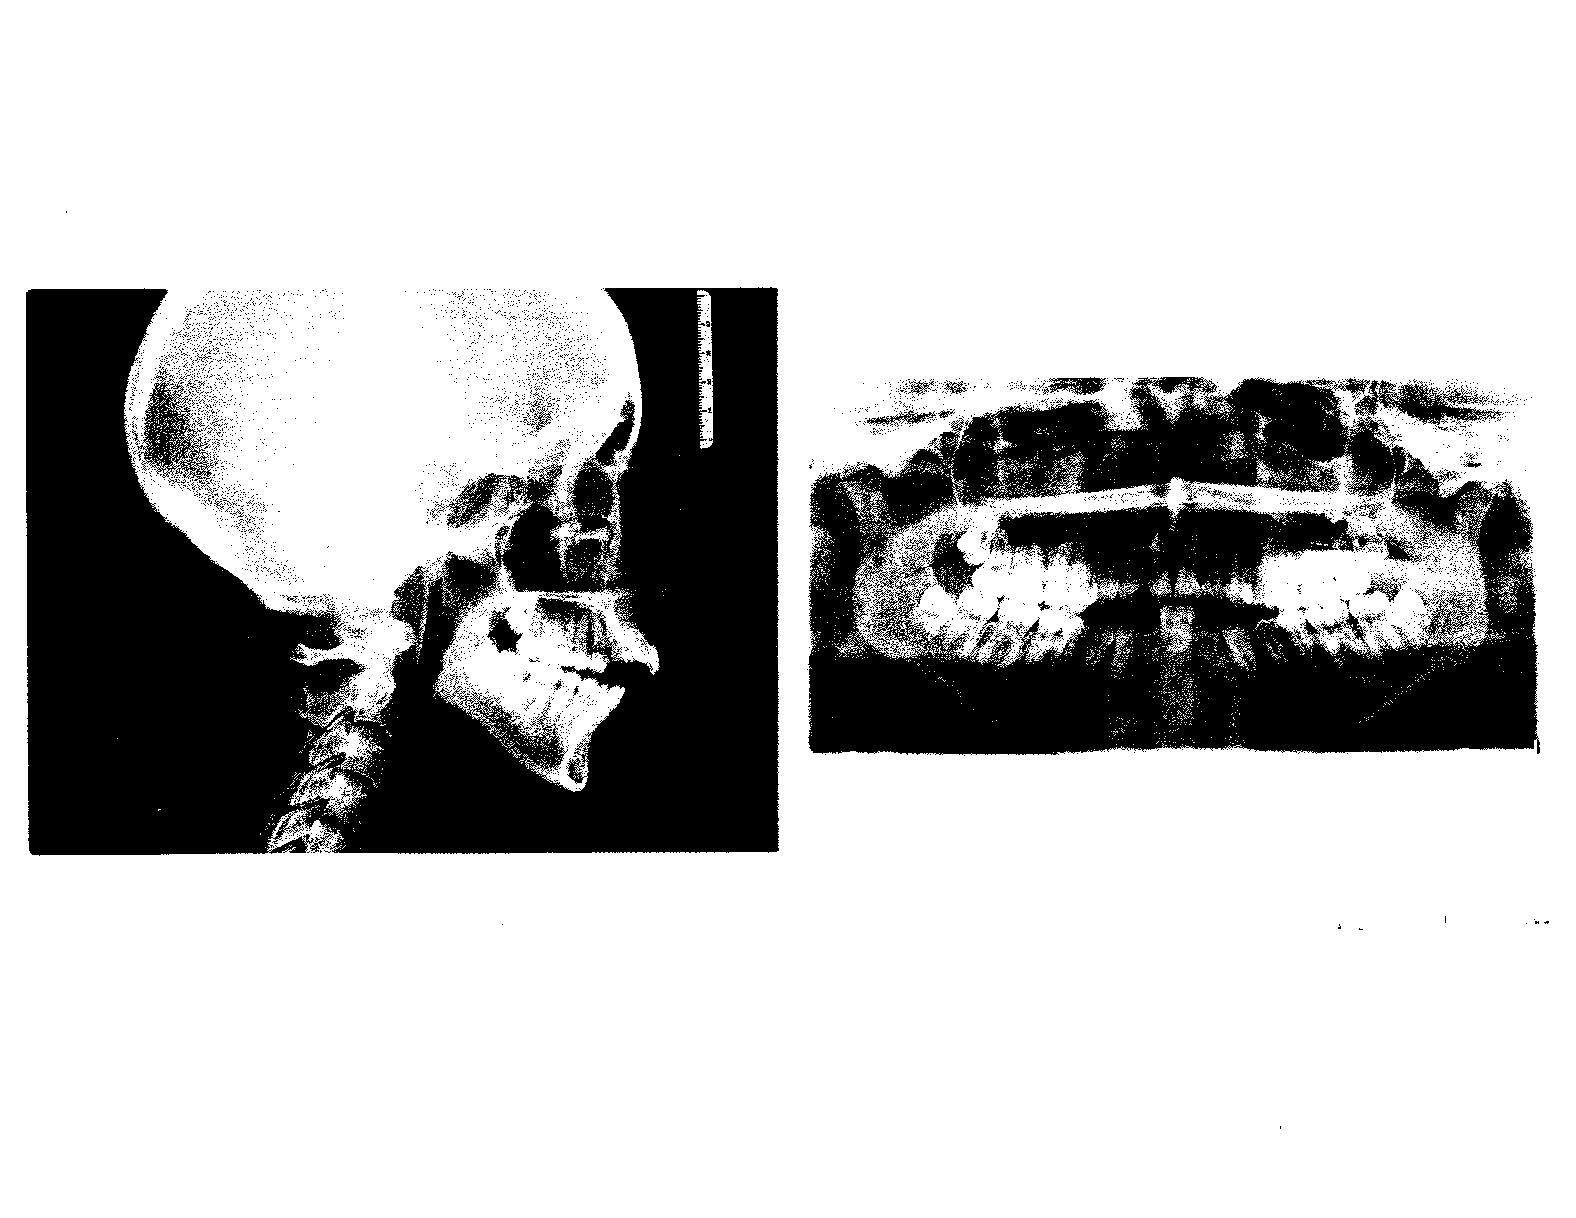

With my background in dentistry, I immediately noticed Alexis’s bite. There was something very different about it. I asked her to close and smile and she had an open bite of approximately 15mm and only touched her back teeth when she was closed. I asked her if I could take a picture and she smiled Big!!

This is where the magic begins. I presented these pictures to Dr. Patel to simply show him the extreme open bite that Alexis has, as I was telling him the story of the hardship she has encountered. He immediately

helping me. I now have braces, my wisdom teeth are out, thank you Dr. Sanders with Dr. Gallia and I’ll be getting jaw surgery in around 10 months. My overbite has caused me severe strife, both mentally and physically. It’s my biggest insecurity and it is also so hard to eat with. I am so excited to know that it is finally happening, my jaw is getting fixed. Thanks to my boyfriend, his parents, and the Dental Society Foundation for having faith in me; I’m in college and am progressing in my life for the first time. I have a car, a house, a job, an amazing dental organization helping me, and a wonderful newfound family that I love very much. These donations have helped save my life. 

wanted to do something! He said, “I’m going to talk to Cathy Levering from the Sacramento Dental Society about Alexis.” The next thing we know Cathy is wanting to help Alexis get her dental needs taken care of. Those needs are extensive, from braces, wisdom teeth extractions and Maxillofacial surgery to realign her jaw. Cathy is an angel with two legs!!